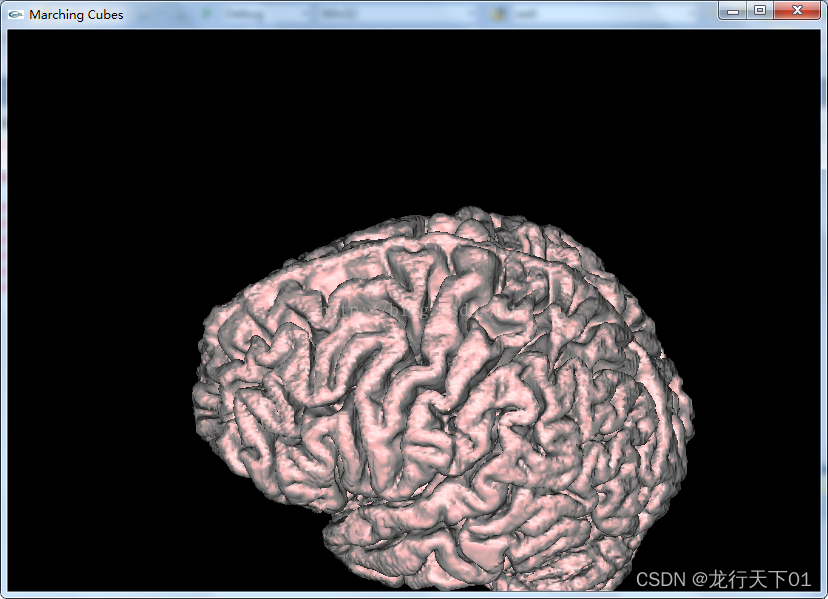

Marching Cube(C++ OpenGl代码)读取医学三维图像*.raw进行三维重建